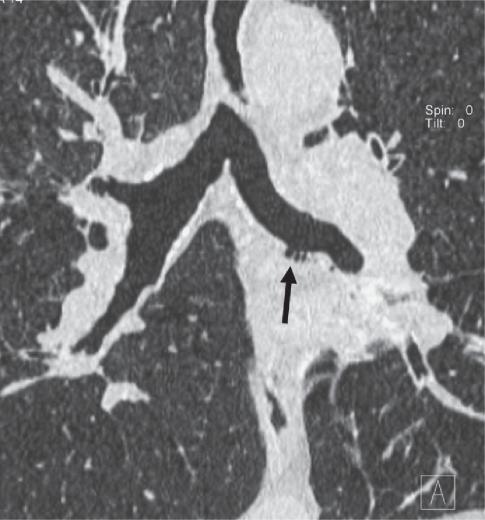

New insights on COPD imaging via CT and MRI.

Multidetector-row computed tomography (MDCT) can be used to quantify morphological features and investigate structure/function relationship in COPD. This approach allows a phenotypical definition of COPD patients, and might improve our understanding of disease pathogenesis and suggest new therapeutical options. In recent years, magnetic resonance imaging (MRI) has also become potentially suitable for the assessment of ventilation, perfusion and respiratory mechanics. This review focuses on the established clinical applications of CT, and novel CT and MRI techniques, which may prove valuable in evaluating the structural and functional damage in COPD.